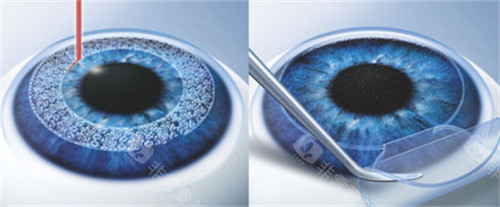

医院采用的手术方式主要有超声乳化白内障吸除术联合人工晶状体植入术等,这些手术方式具有切口小、改善快等优点。

(一)手术方式和材料选择

不同的白内障手术方式和人工晶状体等材料的价格差异较大,这会直接影响报销金额。